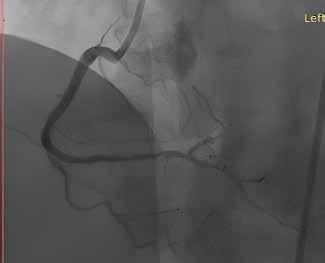

17 Current Use of Drug Coated Balloons for the Complex Coronary Artery Disease Patients

Bernardo Cortese, MD, Interventional Cardiologist, President Scientific Committee, Cardiovascular Research and Innovation Foundation

Jegan Sivalingam, MD, Interventional Cardiologist, Hannah Joseph Hospital

Current Use of Drug Coated Balloons for the Complex Coronary Artery Disease Patients

Drug coated balloon plays a very important role in the management of in-stent restenosis and native coronary artery disease, however its role in the treatment of complex coronary artery disease is an interesting and emerging concept. DCB are available for use in Europe and Asia, but not yet in the USA.

Drug eluting stents (DES) are the mainstay of treatment in a majority of patients with significant stenoses of the coronary arteries. However, the use of DES is associated with various acute and longterm complications such as stent thrombosis, in-stent restenosis (ISR), neoatherosclerosis, and abnormal vasomotion. Moreover, the

implantation of DES mandates the patient to take dual antiplatelet drugs for a certain duration which is not always feasible in all patients and associated with an inherently increased risk in clinically relevant bleedings. Target lesion failure of DES ranges between 0.8-1% yearly in simple lesion subsets itself, with higher rates in the more complex lesion setting. The long-term results of DES are not optimal in complex coronary artery disease subsets such as chronic total occlusion (CTO), complex bifurcation lesions, long lesions, heavily calcific lesions, small vessel coronary artery disease and also, there are no enough studies available assessing the long-term outcomes of DES in this group. Drug coated balloons were initially developed to address the issue of ISR. Later the usage of DCB in treatment of native vessel coronary artery disease increased as it showed favourable long-term outcomes. The use of DCB in complex anatomy is a boon for the patients

as it decreases the duration of DAPT needed and also works on the principle of the “leave nothing behind” strategy: in fact, no metallic cage is left behind in the arteries which in turn facilitates the vessel remodelling and also avoids the stent related complications. The current status of DCB use in complex coronary artery disease is reviewed in this article.

Drug coated balloon overview

Drug coated balloon works on the principle of transferring an antiproliferative drug to the vessel wall upon inflation of the balloon. Paclitaxel is the drug used in the earlier generations of DCBs with a recent introduction of sirolimus.

Adequate lesion preparation is a prerequisite of any percutaneous coronary intervention (PCI) be it stent implantation or DCB application. The lesion is usually predilated with a semi-compliant or non-compliant balloon sized according to the distal vessel

reference size in the ratio of 0.8:1 or 1:1. In case of non-yielding lesions further preparation with normal balloons, cutting or scoring balloons may be required. In heavily calcific lesions the use of rotational or orbital atherectomy, or lithotripsy may be required. The aim of lesion preparation is to achieve less than 30% of residual stenosis with TIMI III flow and no flow limiting dissection prior to the application of DCB.